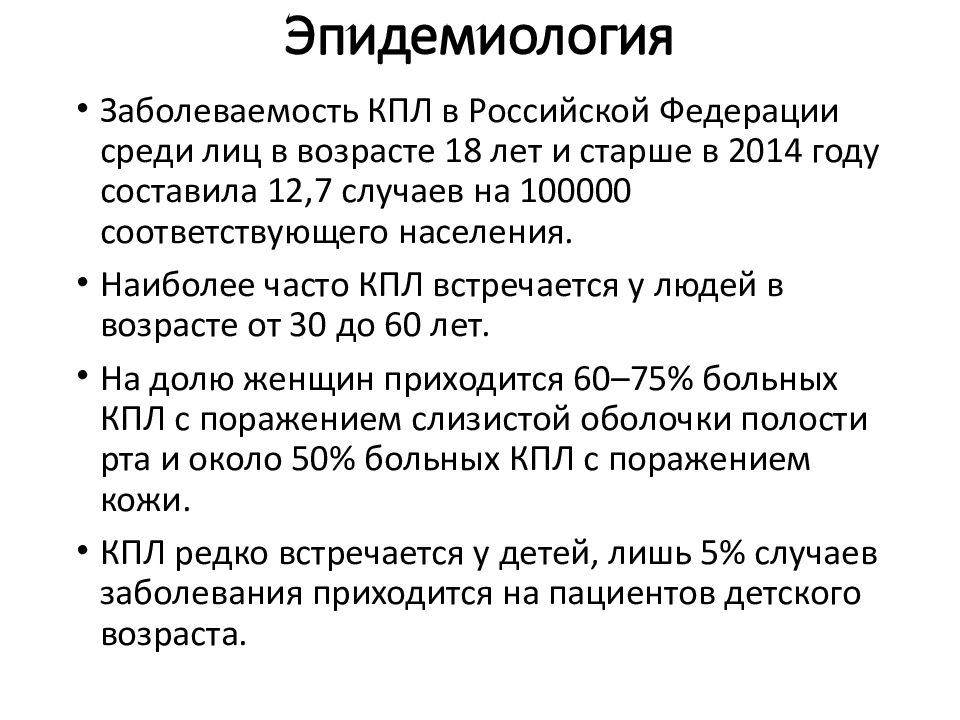

Фото Красного Плоского

Фото Красного Плоского 103 фото